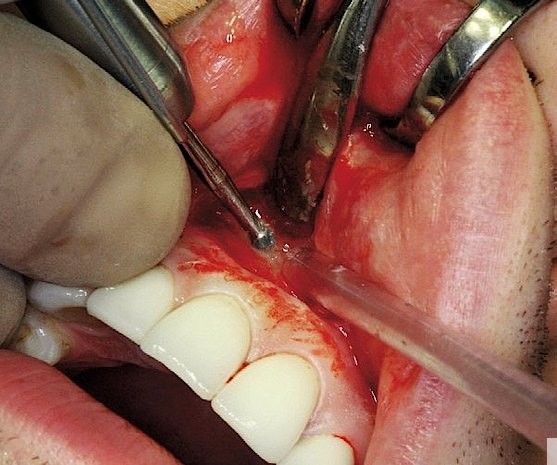

Bu zaman bəzi hallarda kanal müalicəsinin yenidən icrası (endodontik reviziya) mümkün olsa da, bir çox hallarda bu və ya digər səbəbdən həyata keçirilməsi mümkün olmur. Bu zaman əsas tətbiq edilən müalicə metodu dişi çəkməmək şərti ilə, iltihab ocağının uzaqlaşdırılmasını təmin edən – diş kökünün rezeksiyası metodudur. Bu əməliyyat vasitəsilə iltihab ocağı diş kökü ilə birlikdə kənarlaşdırılır və kök kanalları xüsusi metodla yenidən işlənir və doldurulur. Əməliyyat əsasən yerli ağrısızlaşdırma altında, xüsusi böyüdücü vasitənin tətbiqi ilə həyata keçirilir.